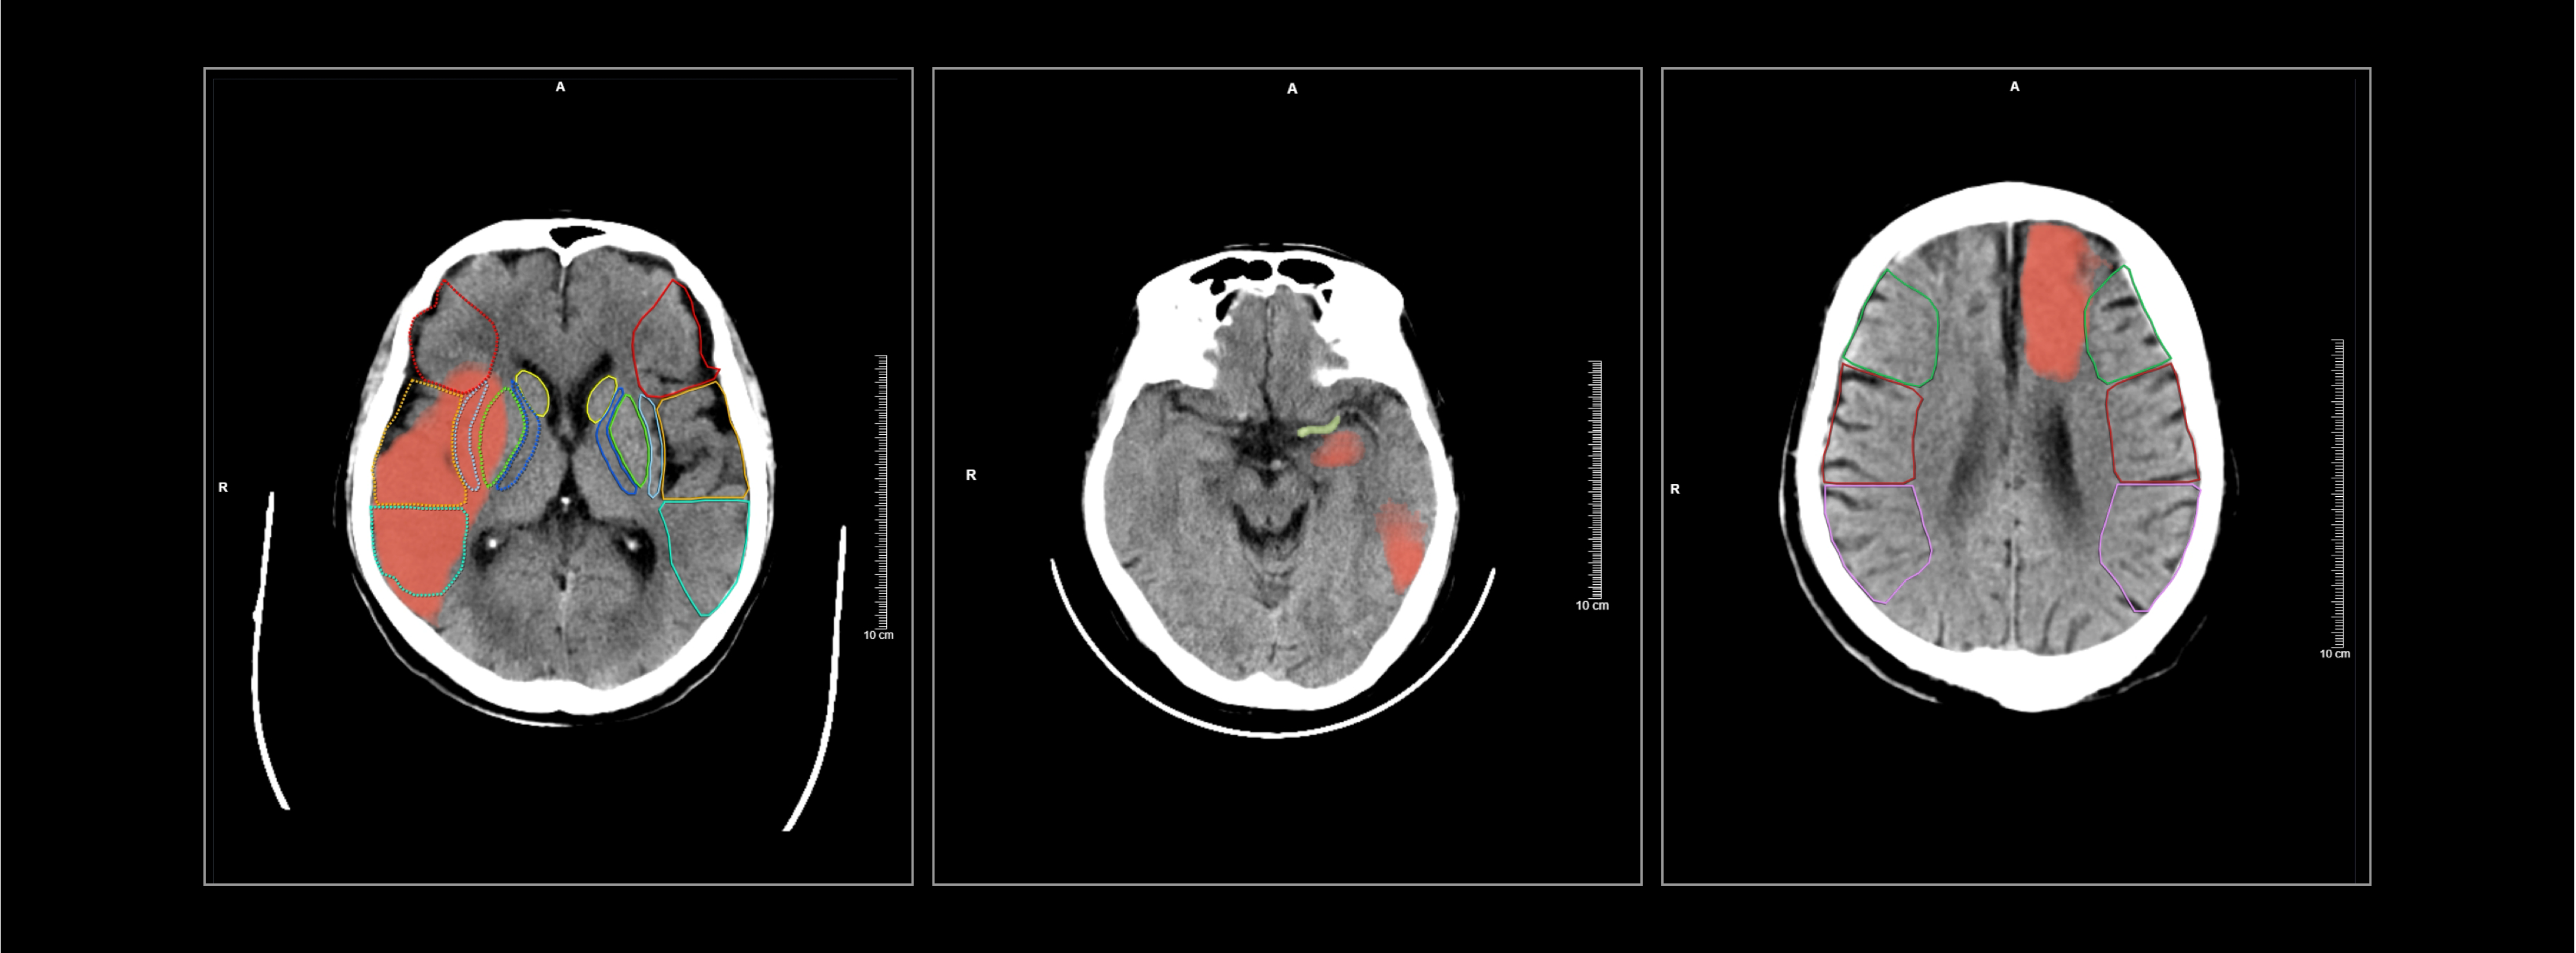

智能识别早期缺血性改变,高亮标记缺血异常区域

精准评估左右脑ASPECTS评分

某三甲医院,一女性患者因突发左侧肢体无力、失语和双眼凝视等症状入院。

医生基于一站式CT扫描结果以及脑缺血AI分析,诊断该患者存在脑缺血情况,右脑ASPECTS评分为6分,有4个受影响区域。值得注意的是,该患者的豆状核和岛叶区域存在缺血问题,但由于早期征象不易识别,医生借助AI辨别发现出这两处区域的缺血情况。